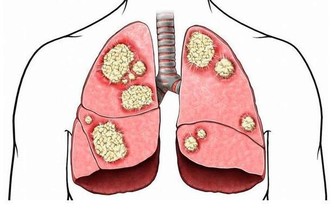

2、癌症

乳腺癌、肺癌、結直腸癌及淋巴癌等癌症在中年人群的發病率也逐年增高。

2、防癌檢查

CT檢查:胸部、頭部。